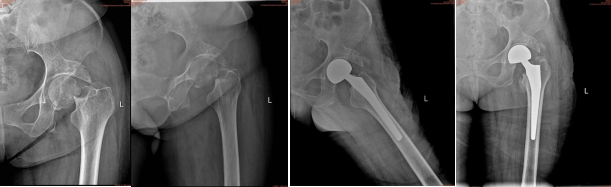

近期,市一医院开发区分院骨科成功为多例特殊患者进行人工髋关节置换术,解除了患者长期卧床的困扰,让患者重新恢复行走活动,极大提高了患者的生活质量。

89岁的患者吴大爷,今年八月初,因在街上步行时不慎滑倒,至左髋疼痛剧烈,活动困难,左下肢不能站立负重行走,后左髋部逐渐肿胀。家属将他送至市一医院开发区分院骨科门诊,经检查诊断为股骨颈骨折,需进行人工髋关节置换,如不做手术,往后可能都需长期卧病在床,在取得家属同意,完善术前检查后, 8月11日在椎管内麻醉下为患者实施了“人工股骨头置换术”,术后恢复良好,第3天即可下地负重行走,患者及家属对治疗效果十分满意。

81岁的患者汪婆婆,因摔伤至左髋部疼痛活动障碍被家人送医院就诊,入院诊断为股骨颈骨折(左)且伴有糖尿病、高血压病3级(极高危)、心功能不全、低钾血症、陈旧性骨盆骨折、陈旧性肱骨骨折(右)、陈旧性尺骨骨折(右)、陈旧性桡骨骨折(右)、胆囊结石、阿尔茨海默病等病症。高龄老人,有三高,心脏功能不好,还患有老年痴呆,加上患者极度不配合给治疗带来了一定难度。经全科讨论及与患者家属沟通后,决定为患者行人工髋关置换术。10月18日在椎管内麻醉下顺利的完成了左侧人工股骨头置换术(半髋关节置换术),患者术后3天恢复行走活动。

53岁的罗女士,有既往烟雾病史,左侧肢体偏瘫后遗症跛行。8月30日在家中不慎摔倒,至左髋部疼痛、畸形、活动困难,左下肢不能负重站立行走,伤后左下肢逐渐肿胀,几天后因上述症状无缓解,于9月4日在市某医院就诊,诊断为左侧股骨颈骨折。为求手术治疗,9月6日转入市一医院开发区分院骨科,经医生诊断有股骨颈骨折(左侧)、烟雾病、左侧肢体偏瘫、尿路感染、肺部感染、左下肢深静脉血栓形成、脂肪肝、肝囊肿、双肾结石、胆囊结石、膀胱结石等病症。与家属沟通后,经骨科全体医生讨论制定手术方案,决定为患者行左侧半髋关节置换术,10月18日在手术室医生护士的配合下,顺利的完成了该项手术,术后4天可下地负重行走。专家提醒,当老年人髋部受伤、患肢不敢活动时一定要及时就医。

71岁的彭婆婆, 10月30日在家中上厕所时摔倒,左臀部先触地,当即感左髋疼痛剧烈,活动困难,不能站立行走。入院后诊断为股骨颈骨折(左侧、头下型),且伴有腰椎退行变、右小腿烫伤(二度)、脑溢血后遗症、高血压3级(极高危)、糖尿病、乙肝小三阳、脑梗、左侧偏瘫、肝囊肿、左肾囊肿、偶发室上性早搏、窦性心律不齐、双侧颈动脉斑块形成、双下肢动脉板块形成、阿尔茨海默病(老年型前期)。家属经过多次商量后决定行手术治疗,11月03日顺利完成半髋关节置换术,术后4天下地活动,解决了患者痛苦,极大提高了患者的生活质量。